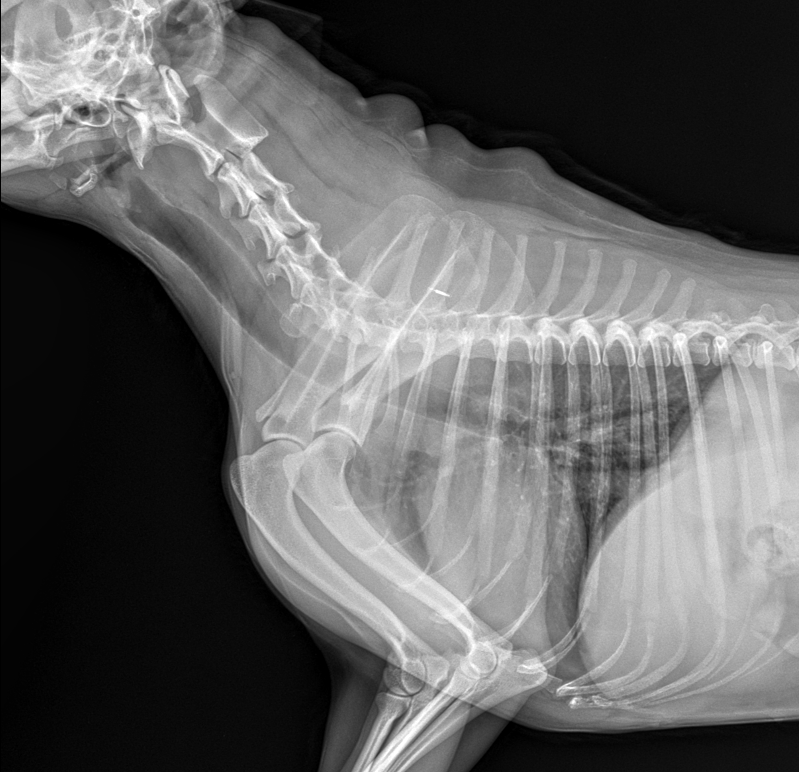

엑스레이를 찍었는데 폐에 물이 찬건가요???

저번주 주말에 찍은 엑스레이입니다.

건강검진 받을 땐 심장이 좀 부어있다고

영양재 주면서 관리만 잘하라고 했어요

올해 검사했을땐 재작년 보다 정말 희미하게

사이즈가 줄었구요ㅠㅠ.. 근데 애기 호흡수가

빨라져서 엑스레이 비교하면서 이것 저것 찾아봤는데

혹시 폐에 물이찬게 아닌가 걱정이 됩니다

엑스레이의 경우 조건을 잘 맞춰고 최대 흡기떄 촬영읋 했을 조건에는 폐가 그렇게 좋아 보이지는 않습니다.

그래도 심장의 크기는 그렇게 커보이지는 않네요

과거 심장병 진단을 받으셨으면 흉부 방사선 외에 심장 초음파도 한번 촬영해보시기 바랍니다.

폐수종을 의심할 수준의 폐 침윤 양상은 관찰되지 않으나

무정형의 간질성 침윤 양상이 관찰되어 노령성변화나 기관지염, 섬유화증 등을 의심할 수 있는 영상입니다.

다만 증상이 비특이적이라 노령성 변화 가능성이 가장 높은것으로 보입니다.